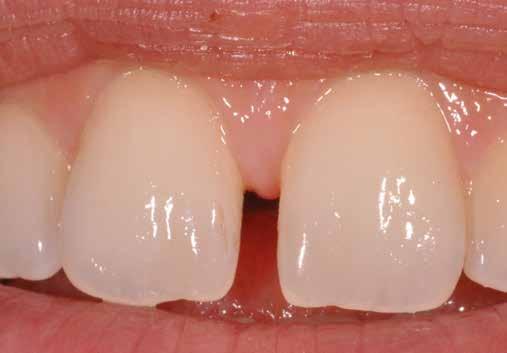

ezen a területen, a fogászat profitál az ilyen fejlesztésekből, és ma már számos kezelési megoldást kínálunk pácienseinknek. Rezidens korom alatt klinikai szakfelügyelőként dolgoztam akadémiai környezetben, ahol elsősorban kivehető fogpótlásra szoruló geriátriai betegeket kezeltem, valamint olyanokat, akiknek fix fogpótlásra, például fog- vagy implantátummal ellátott hagyományos rögzített fogpótlásra (azaz korona és híd) volt szükségük, elsősorban arany vagy fémkerámia felhasználásával. Az ezekben az években megfigyelt klinikai kudarcok és a beavatkozások invazív jellege, nevezetesen a foghúzásra vonatkozó több fúrás és egyszerűbb döntések jelentős szerepet játszottak a kutatási irányvonalam kialakításában az évek során. Ez volt az az időszak is, amikor elkezdtem többet foglalkozni az adhezív fogászattal, ami megváltoztatta a protetikai fogászat klasszikus arculatát, és határozottan kevésbé invazívvá tette azt (1. a-d ábrák). Ma, az intenzív transzlációs és klinikai kutatás eredményeként, különös tekintettel a fogászati bioanyagok alkalmazására, klinikai szakértelmem a minimálisan invazív, adhezív eljárások alkalmazására összpontosít a protetikai fogászatban, a szövődmények kezelésére és a költséghatékony kezelési lehetőségek felkínálására.

1. a-d ábrák: a) Fogerózió a molárisok okkluzális felszínén, b) maratás foszforsavval, c) minimálisan invazív műgyanta-kompozit fedőréteg levegővel történő felszívása, d) adhezív ragasztott fedőréteg a hiányzó zománc és dentin helyreállítására.